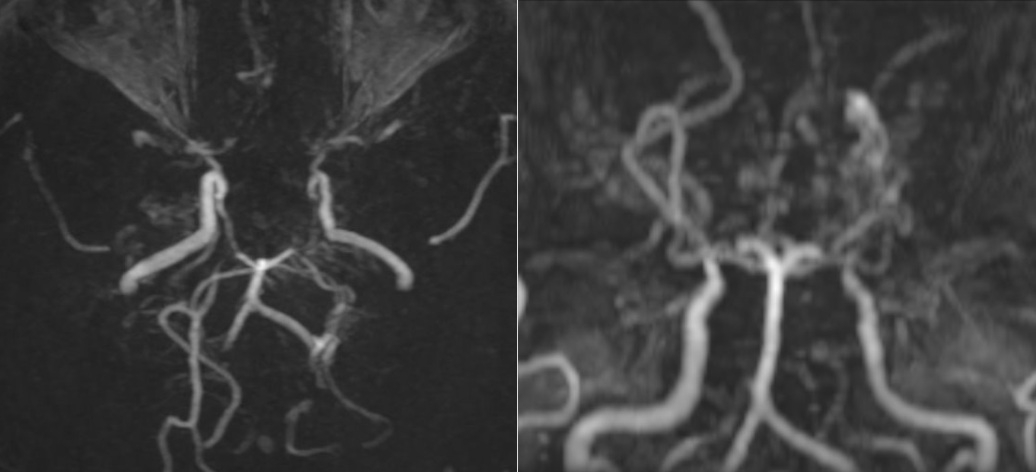

Các mạch máu não của bệnh nhân nhìn như “làn khói thuốc lá” trên phim chụp MRI.

nguyên nhân, bác sĩ chỉ định chụp cộng hưởng từ (MRI) sọ não. Kết quả MRI cho

thấy, hình ảnh tổn thương hẹp tắc động mạch cảnh trong hai bên và các nhánh của

đa giác Willis, xung quanh hình thành tuần hoàn bàng hệ với nhiều mạch máu nhỏ

bất thường.

Đồng thời, trên chuỗi xung FLAIR, xuất hiện những dải tín hiệu

sáng chạy dọc theo rãnh cuộn não, gợi hình ảnh “dây thường xuân” len lỏi trên bề

mặt, phản ánh sự gia tăng tuần hoàn bàng hệ màng mềm để bù đắp cho tình trạng

thiếu máu não do tắc nhánh mạch não. Bên cạnh đó, bác sĩ cũng phát hiện một

hình ảnh tổn thương cũ ở vùng trán trái, là biến chứng của bệnh lý Moyamoya.